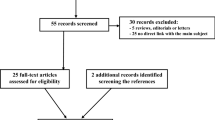

An institutional review board waiver was obtained for this retrospective study analysis since for this type of study formal ethical approval is not required. Informed consent was obtained from all individual participants included in the study. This single-institution pilot study used archived patient data previously obtained in routine diagnostic practice. Consecutive patients diagnosed with pathologically proven, newly diagnosed Hodgkin’s or high-grade non-Hodgkin’s lymphoma and treated at our institution from 2007 to 2013 were identified from the institutional lymphoma database. Inclusion criterion was that subjects were newly diagnosed Hodgkin’s or high-grade non-Hodgkin’s lymphoma patients who had a pre-treatment PET-CT scan performed before chemotherapy. Based on the above inclusion criterion, 45 patients were included in our study population (20 men and 25 women, mean age: 52, age range 22–81 years).